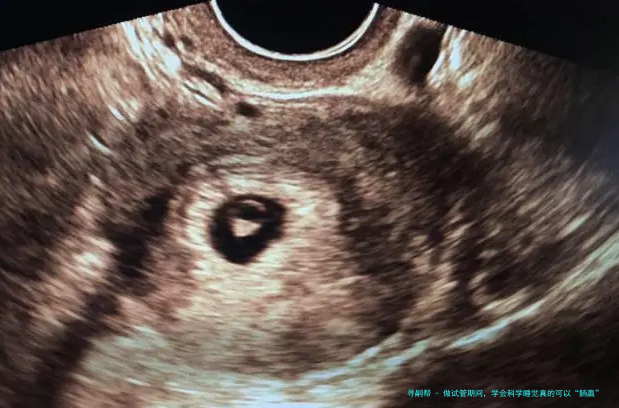

⑴在促排卵期间,可以适当多休息,但是预防长时间坐、久卧等情况,影响到身体健康和促排卵效果。促排卵用药后,女性的卵巢内多颗基础卵泡的发育,以及内里激素水平发生变化,此时女性可能会有萎顿感,可分频繁短暂时间地坐卧休憩,但是应注意掌控时间,并且按时用饭和如厕。按时睡醒活动身体,不仅有益于身体血液的反复,还可改善胃口,提高卵巢对促排用药的反响,从而提高获卵数目和素养。于采卵术后要躺床休息6—8小时,随后就可以痊愈正常的生活,纪律作息、做好卫生管理防备创口感染、避免身体疲劳和激烈运动就可以。

二、胚胎移植后。从医院抵家休息,要严密按医嘱躺床休憩满48小时,因为这个时间是囊胚移植后游离寻找俱佳着床位置的时间段,充分在床上休憩的要求是准妈妈除了正常的吃饭和如厕外,都须要十足卧床休息,在床上姿势可以是平卧、侧躺或斜卧,注意斜卧的姿势要小于四十五度。如厕时要抉择坐便的方式,避免深蹲、身体动作幅度大而影响到囊胚的游离,防备异位妊娠或滑胎的出现。48小时之后,就能正常生活和事业了,防止久卧对身体血液、心理压力、睡眠、身体代谢和排毒素等方面的影响,反而不利于胚胎的着床和胎儿健康发育。尚有少许,便是维系轻快愉悦的心态,相信并对试管婴儿抱有等待,如此结果就可以正向发展了。